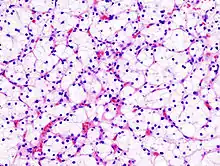

Papillary Renal Cell Carcinoma (PRCC)

![]() Type 1 PRCC consist of papillae covered with a single or double layer of small cuboid cells with scanty cytoplasm and Type 2 PRCC consist of papillae covered by large eosinophilic cells arranged in an irregular or pseudostratified manner. |

10–15% |